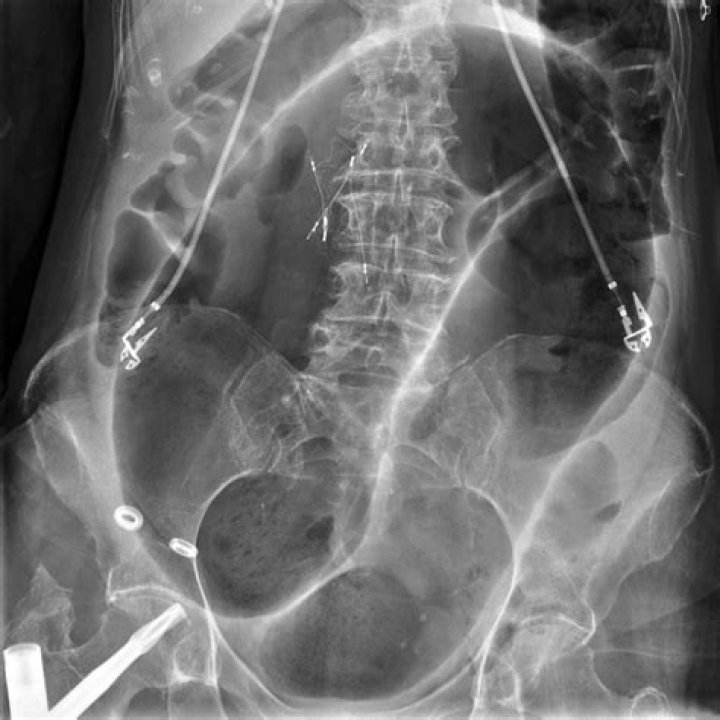

Sigmoid Volvulus on Abdominal X ray

Plain abdominal radiographic findings are usually diagnostic of sigmoid volvulus. Decompression may be achieved by the introduction of a stiff tube per rectum, aided by endoscopy or fluoroscopy. A single-contrast barium enema examination is usually adequate if it is required, as in cases when the diagnosis is in doubt.

A definitive sign of a cecal volvulus is the upward displacement of the appendix with obstruction of the large bowel. Comparatively, a sigmoid volvulus will show findings of a bent inner tube sign with the apex of the volvulus located in the left upper quadrant.